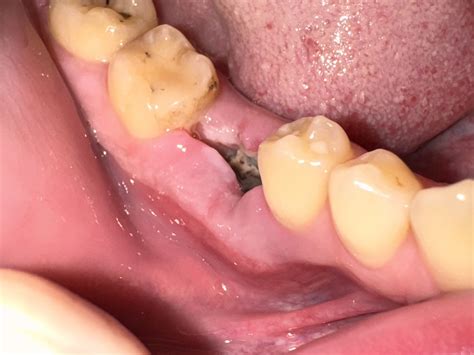

Few dental experiences are as intimidating or painful as dealing with a severe dental abscess. When a tooth is compromised by deep decay, trauma, or gum disease, bacteria can enter the pulp chamber, leading to a serious infection. In many cases, dentists aim to save the natural tooth; however, there are scenarios where an infected tooth extraction becomes the only viable solution to prevent the infection from spreading to the jawbone, bloodstream, or other parts of the body. Understanding the process, the risks, and the recovery period is essential for anyone facing this common yet significant dental procedure.

An infected tooth extraction is typically recommended when a tooth is so severely damaged by decay or infection that it cannot be restored. While procedures like root canal therapy are often the first line of defense, they are not always successful or applicable depending on the extent of the infection. When the infection reaches a critical stage, leaving the tooth in the mouth poses a severe risk to your systemic health.

• infected tooth extraction site pictures